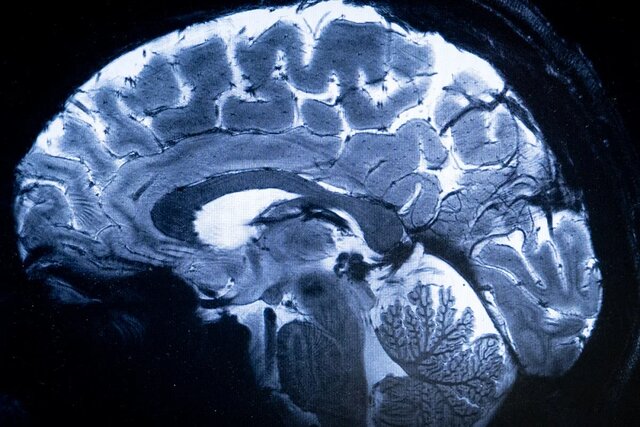

با حمایت ستاد توسعه علوم شناختی، چهاردهمین کنگره علوم اعصاب پایه و بالینی از ۱۹ تا ۲۱ آذر در دانشگاه علوم پزشکی ایران برگزار می‌شود تا آخرین دستاوردهای پژوهشی در حوزه پزشکی شخصی‌سازی شده معرفی شود.

به گزارش نمابان و به نقل از ایسنا، چهاردهمین کنگره علوم اعصاب پایه و بالینی به منظور توسعه فعالیت‌های پژوهشی، تبادل آخرین دستاوردها و یافته‌ های تحقیقاتی و نیز گسترش تعامل و همکاری میان محققان، متخصصان و پژوهشگران با حمایت ستاد توسعه علوم و فناوری‌های شناختی از ۱۹ تا ۲۱ آذرماه در محل مرکز همایش‌های بین المللی رازی دانشگاه علوم پزشکی ایران برگزار می شود.

این کنگره با محوریت “پزشکی شخصی سازی شده”، فرصت مناسبی را برای محققان، پزشکان، دانشجویان و متخصصان فعال در زمینه علوم اعصاب پایه و بالینی فراهم می سازد تا در محیطی پویا به بحث و تبادل نظر، انتقال تجربه و اندیشه ورزی بپردازند و از این رهگذر پیوند بین تحقیقات علوم پایه و کاربردهای بالینی را در فضایی بین رشته ای تقویت کنند.

ارائه جدیدترین دستاوردهای علمی و نتایج تحقیقاتی با حضور متخصصان برجسته داخلی و بین‌المللی در تمامی رشته‌های مرتبط از مهندسی تا پزشکی و علوم انسانی از رویکردهای این گردهمایی تخصصی به شمار می رود.